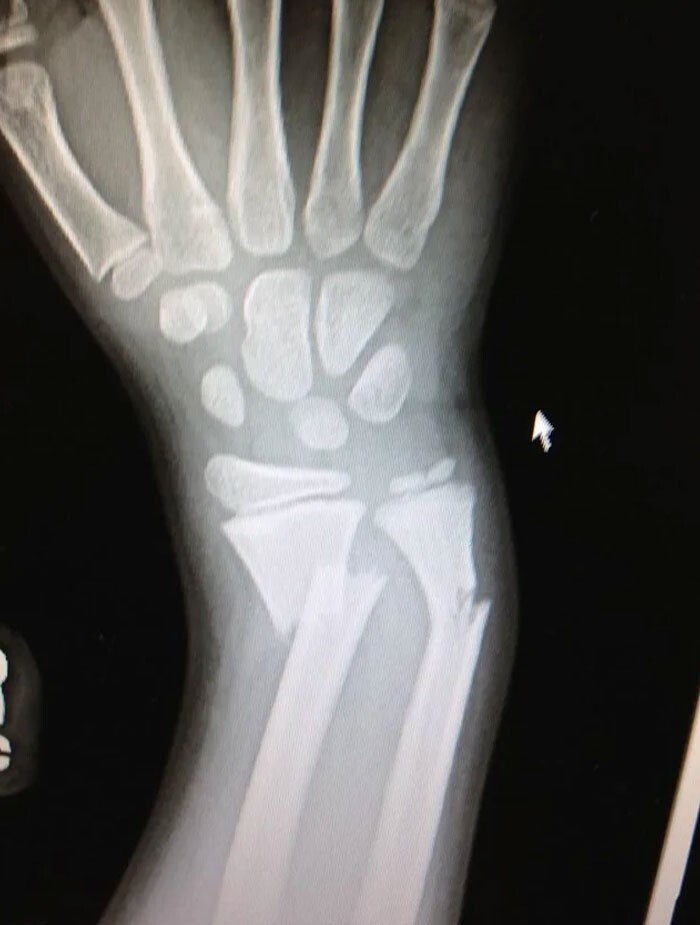

24. "Рентгеновский снимок моего перелома руки в детстве"